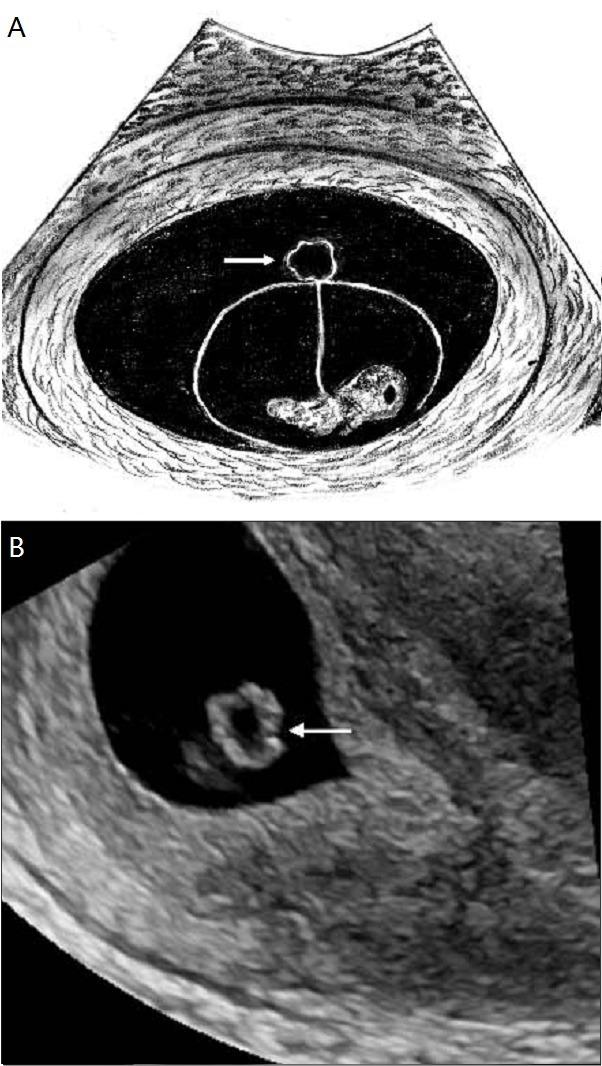

b 为妊娠 6 6 周时经阴道超声显示胚胎死亡(箭头),其外部未见卵黄囊

图 b 为妊娠 6 6 周经阴道超声显示存活胚胎及不规则的卵黄囊图 12